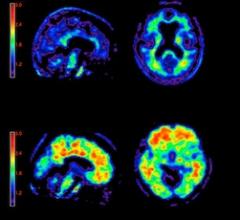

May 18, 2012 — In April the U.S. Food and Drug Administration (FDA) approved Avid Radiopharmaceuticals’ (now part of Eli Lilly) Amyvid, a brain plaque diagnostic tool using florbetapir (F-AV-45). This radiotracer agent is delivered intravenously and is drawn to beta-amyloid plaque, a characteristic of AD.

Several positron emission tomography (PET) imaging agents are being developed to visualize Alzheimer’s disease in the living brain to accurately diagnose patients and develop effective treatments. The only way to confirm the presence of the disease currently is by examining post-mortem samples of the patient’s brain. Experts predict these agents may soon receive U.S. Food and Drug Administration (FDA) clearance.